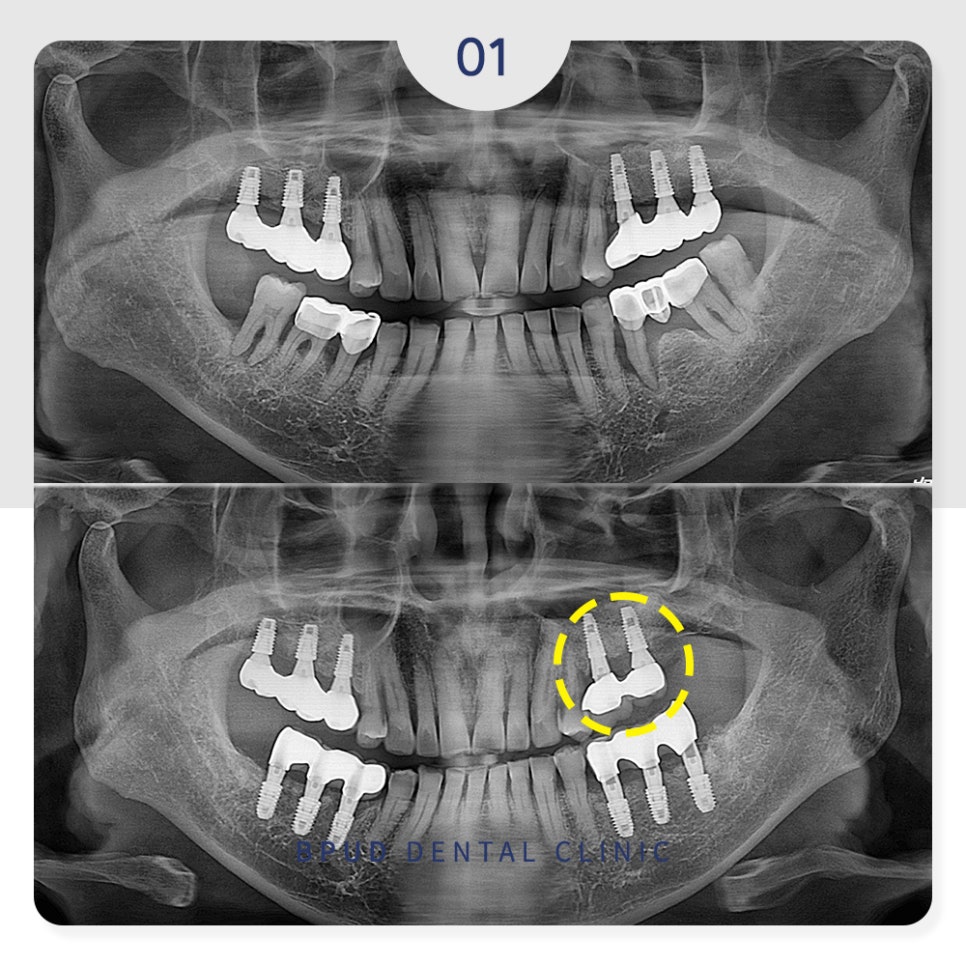

오늘은 아래 임플란트 수복 진행 후

상악동 내 임플란트가 빠져

재수복을 진행하신

부평치과 부평유디치과의 환자분을

소개해 드리도록 하겠습니다.

22.08.26

아래쪽은 다행히도 큰 문제 없이

발치 후 식립과 최종 보철물의

합착까지 마무리하였습니다.

24.05.17

24.06.29

대학병원에 가서 큰 수술을 받아야 하는

것으로 생각하고 계셨던 환자분께서는

제거가 가능하여 너무 감사하다는 말씀을

해주셨고 앞으로는 정기적으로 내원하시겠다는

약속을 해주셨습니다.